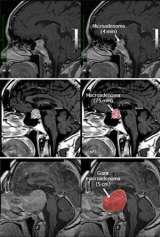

- Size. A microadenoma is less than one centimeter in size; a macroadenoma is one centimeter or greater in size.

One method we use to detect pituitary adenomas is a magnetic resonance imaging (MRI) scan. An MRI can reliably detect adenomas larger than four millimeters. We use a special pituitary protocol to help obtain an accurate image. In some cases, a powerful 3T (Tesla) MRI scanner may detect even smaller tumors not visible during a regular MRI scan. MRI is the preferred imaging scan for detecting pituitary adenomas, though sometimes a computed tomography (CT) scan is used.